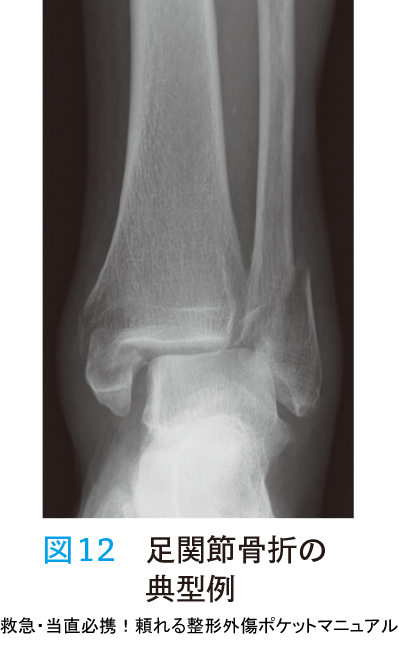

- 足関節は回旋による介達外力による損傷を受けやすく,靱帯断裂または距骨転位により骨折が発生する(図12).